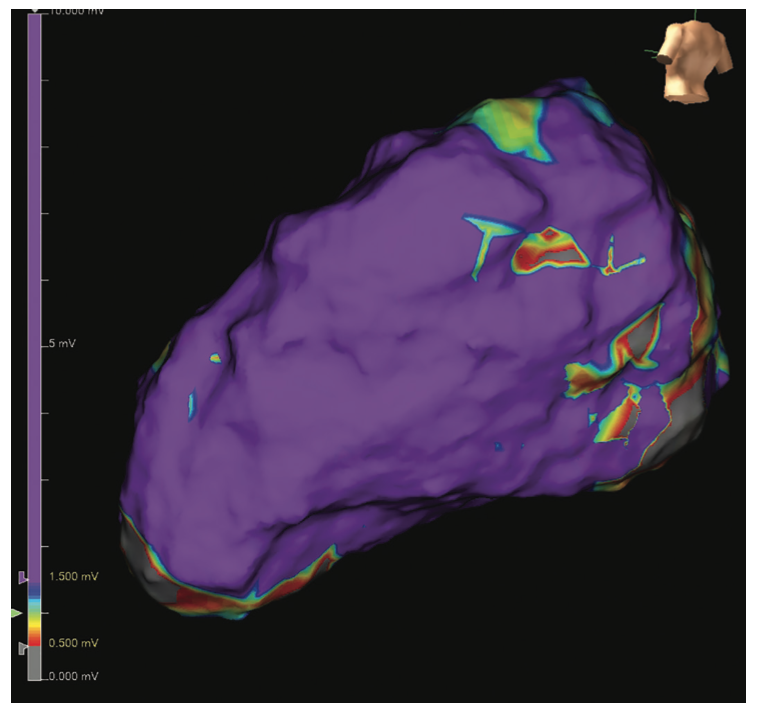

All of these maps are individually analyzed in the context of the voltage map to determine the most pertinent areas of the patient’s scar. Transseptal access was then obtained and an endocardial voltage map of the LV was created with the Advisor HD Grid. This showed normal voltage with no areas of LPs or LAVAs (Figure 5). All of the interesting signals were in the epicardial lateral LV.